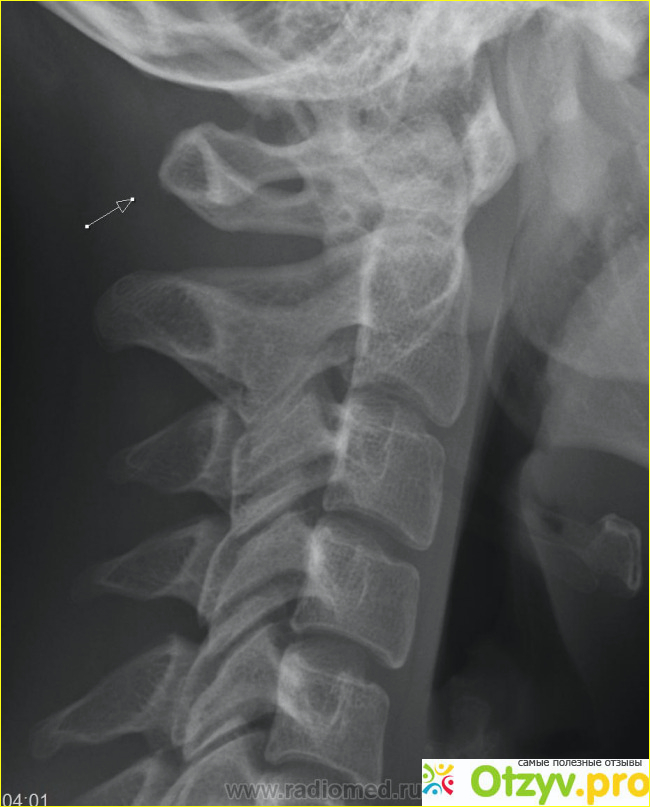

Речь идет об отростке в шейном отделе, в основном это второй позвонок, в норме он быть в форме полукольца или кольца не должен, в этом и заключается аномалия. Просто в этом месте выходит позвоночная артерия к черепу, которая кровоснабжает головной мозг. Из за этой аномалии артерия может слега быть передавленной и кровь поступает не в полном объеме и соответственно мозг страдает от гипоксии (кислородное голодание). Отсюда с вытекающимися последствиями приобретаются заболевания малоприятные, например инсульт. Головной мозг у человека управляет всем организмом, вот и представьте если ваш рулевой не в порядке, то каково будет управление. Произойдет дезорганизация, и так все будет работать, а порой человек так и живет с аномалией и некоторые врачи не обследуют пациента не вспоминая о такой проблеме, как вы уже поняли очень серьезной.

Если имеется аномалия Киммерли , могу появиться такие симптомы, как головокружение, шум в ушах, мелькание мошек перед глазами, при перенапряжении мышц шеи и резких поворотах головы, человек может упасть в обморок. Присутствуют другие симптомы тремор конечностей, онемение половины лица, нарушение чувствительности рук или одной руки и это не не все симптомы. Чтобы выявить у пациента этот недуг врач назначает ряд обследований: рентгенографию черпа и позвоночной артерии, доплеровское и дуплексное сканирование, вообщем провести диагностику всех сосудов которые кровоснабжают мозг. Назначается медикаментозное лечение, ставятся ноотропные препараты, витаминотерапия и другие. Врач подберет для вас с вязи с переносимостью вами препараты, чтобы улучшить работу головного мозга и он для вас постарается работать, как часы. Обязательно нужно соблюдать режим работы и отдыха. Для того чтобы мозговой компьютер не вышел из строя. Запрещены категорически стойки на голове, играть в футбол и те занятия физические и виды спорта, где вовлекается голова и шея. Данное заболевание распознает невролог, именно к нему нужно записываться, а он может направить на курс лечебного массажа, в этом случае он был бы кстати. Повезет вам если вы попадете к грамотному специалисту, потому что при данной аномалии нельзя выполнять массаж грубо и применять усилия, то есть силу. Здесь в задачу массажиста входит расслабить мышцы шеи, верхней части головы и надплечья, для того что бы улучшить кровоснабжение.